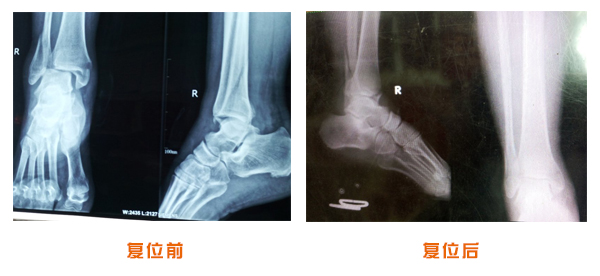

踝關節脫位骨折治療前后對比

尺橈骨骨折治療前后